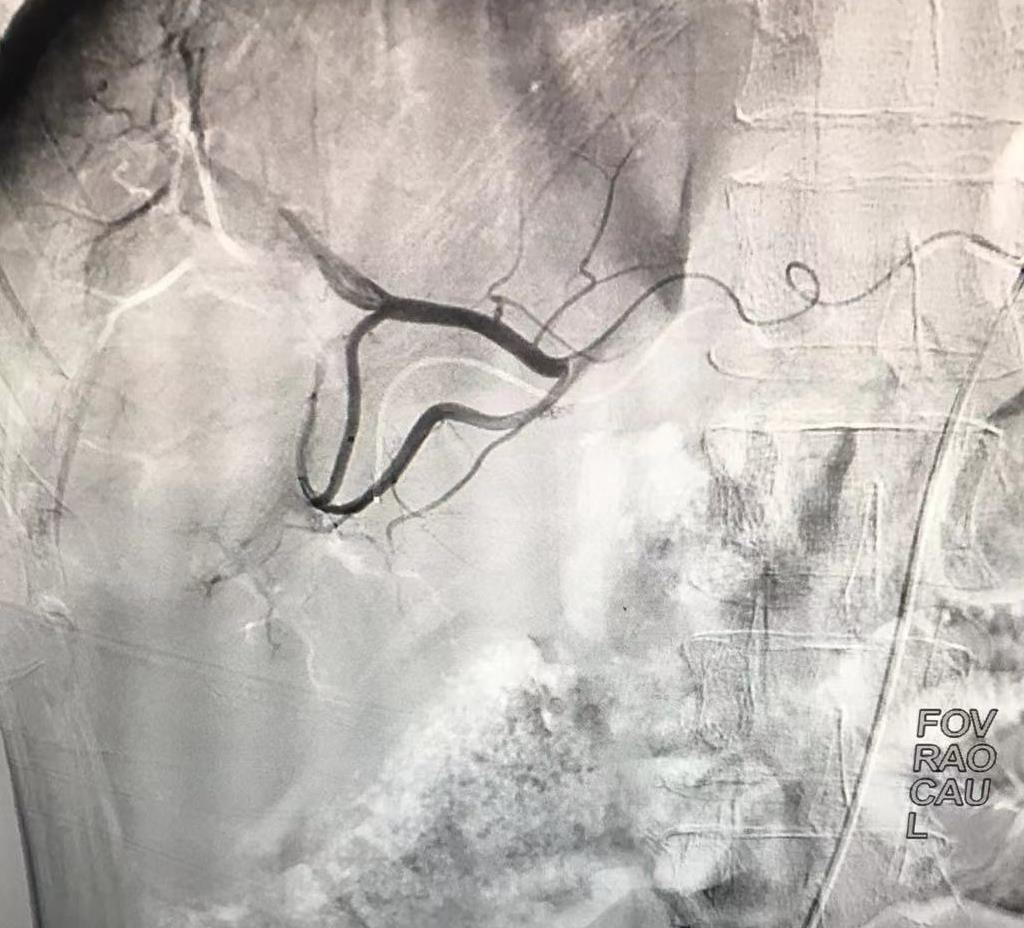

術(shù)前造影顯示腫瘤由肝動脈分支供血,血管增粗屈曲,腫瘤染色顯影明顯。